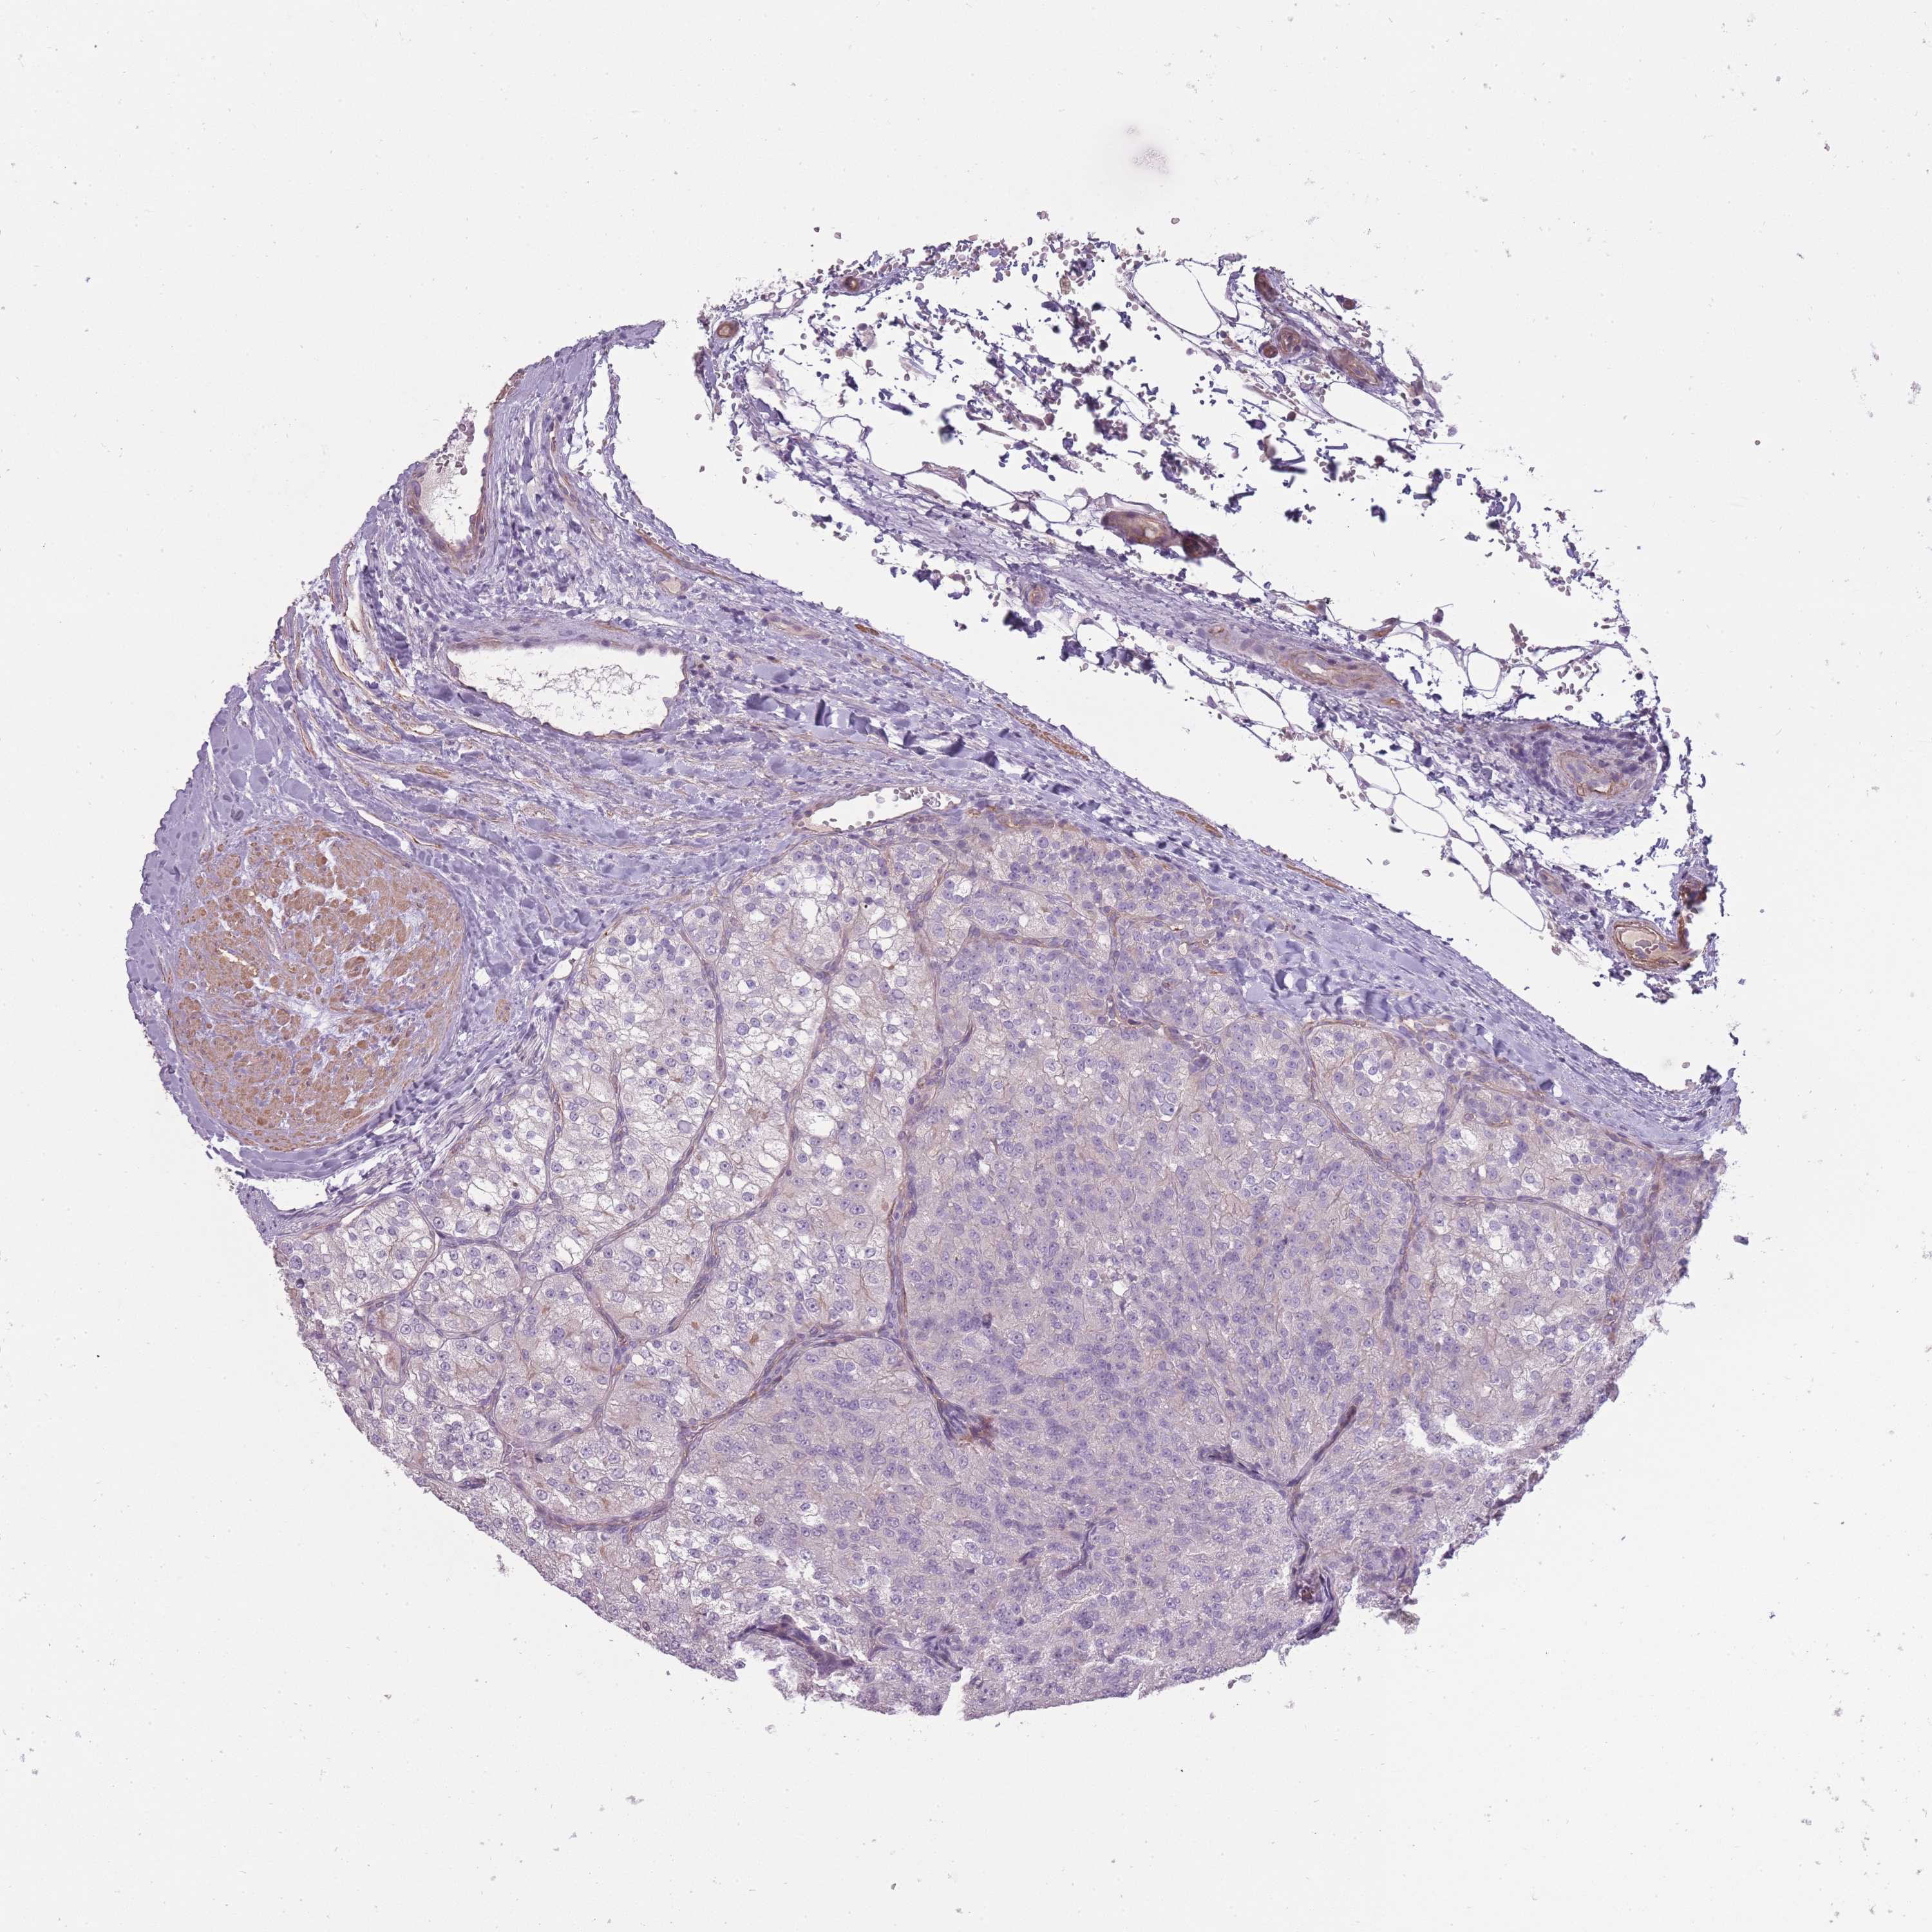

KIDNEY RENAL CLEAR CELL CARCINOMA (VALIDATION) - Interactive survival scatter ploti

The Survival Scatter plot shows the clinical status (i.e. dead or alive) for all individuals in the patient cohort, based on the same data that underlies the corresponding Kaplan-Meier plots. Patients that are alive at last time for follow-up are shown in blue and patients who have died during the study are shown in red.

The x-axis shows the expression levels (FPKM) of the investigated gene in the tumor tissue at the time of diagnosis. The y-axis shows the follow-up time after diagnosis (years). Both axes are complimented with kernel density curves demonstrating the data density over the axes. The top density plot shows the expression levels (FPKM) distribution among dead (red) and alive patients (blue). The right density plot shows the data density of the survived years of dead patients with high and low expression levels respectively, stratified using the cutoff indicated by the vertical dashed line through the Survival Scatter plot. This cutoff is automatically defined based on the FPKM cutoff that minimizes the p-score. The cutoff can be changed by dragging the vertical line or by entering a cutoff value in the square labeled "Current cut-off".

Under the Survival Scatter plot the p-score landscape (black curve; left axis) is shown together with dead median separation (red curve; right axis). Dead median separation is the difference in median mRNA expression between patients who have died with high and low expression, respectively. It is calculated as follows: median FPKM expression of dead patients with high expression - median FPKM expression of dead patients with low expression. This is intended to aid the user in visually exploring custom cutoffs and the associated p-scores and dead median separation.

Individual patient data is displayed and can be filtered by clicking on one or more of the category buttons on the top of the page. Categories describing expression level and patient information include: high, low, alive, dead, female, male and tumor stages. The scale of the x-axis can be toggled between linear and log-scale by clicking on the "x log" button. Mouse-over function shows TCGA ID, patient information and mRNA expression (FPKM) for each patient.

& Survival analysisi

Kaplan-Meier plots summarize results from analysis of correlation between mRNA expression level and patient survival. Patients were divided based on level of expression into one of the two groups "low" (under cut off) or "high" (over cut off). X-axis shows time for survival (years) and y-axis shows the probability of survival, where 1.0 corresponds to 100 percent.

SLC8A2 is not prognostic in Kidney Renal Clear Cell Carcinoma (validation)

TCGA RNA samplesi

RNA-seq data is reported as average FPKM (number Fragments Per Kilobase of exon per Million reads), generated by the The Cancer Genome Atlas (TCGA) .

Normal distribution across the dataset is visualized with box plots, shown as median and 25th and 75th percentiles. Points are displayed as outliers if they are above or below 1.5 times the interquartile range. FPKM values of the individual samples are presented next to the box plot.

Average pTPM 0.0

Number of samples 100